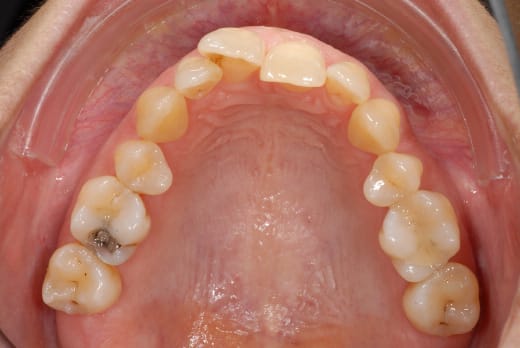

ben voilà des news en photo...

(et que personne me sape le moral...)

00184904 vui1ji - Eugenol

00184919 s85o5f - Eugenol

00184924 r1np2u - Eugenol